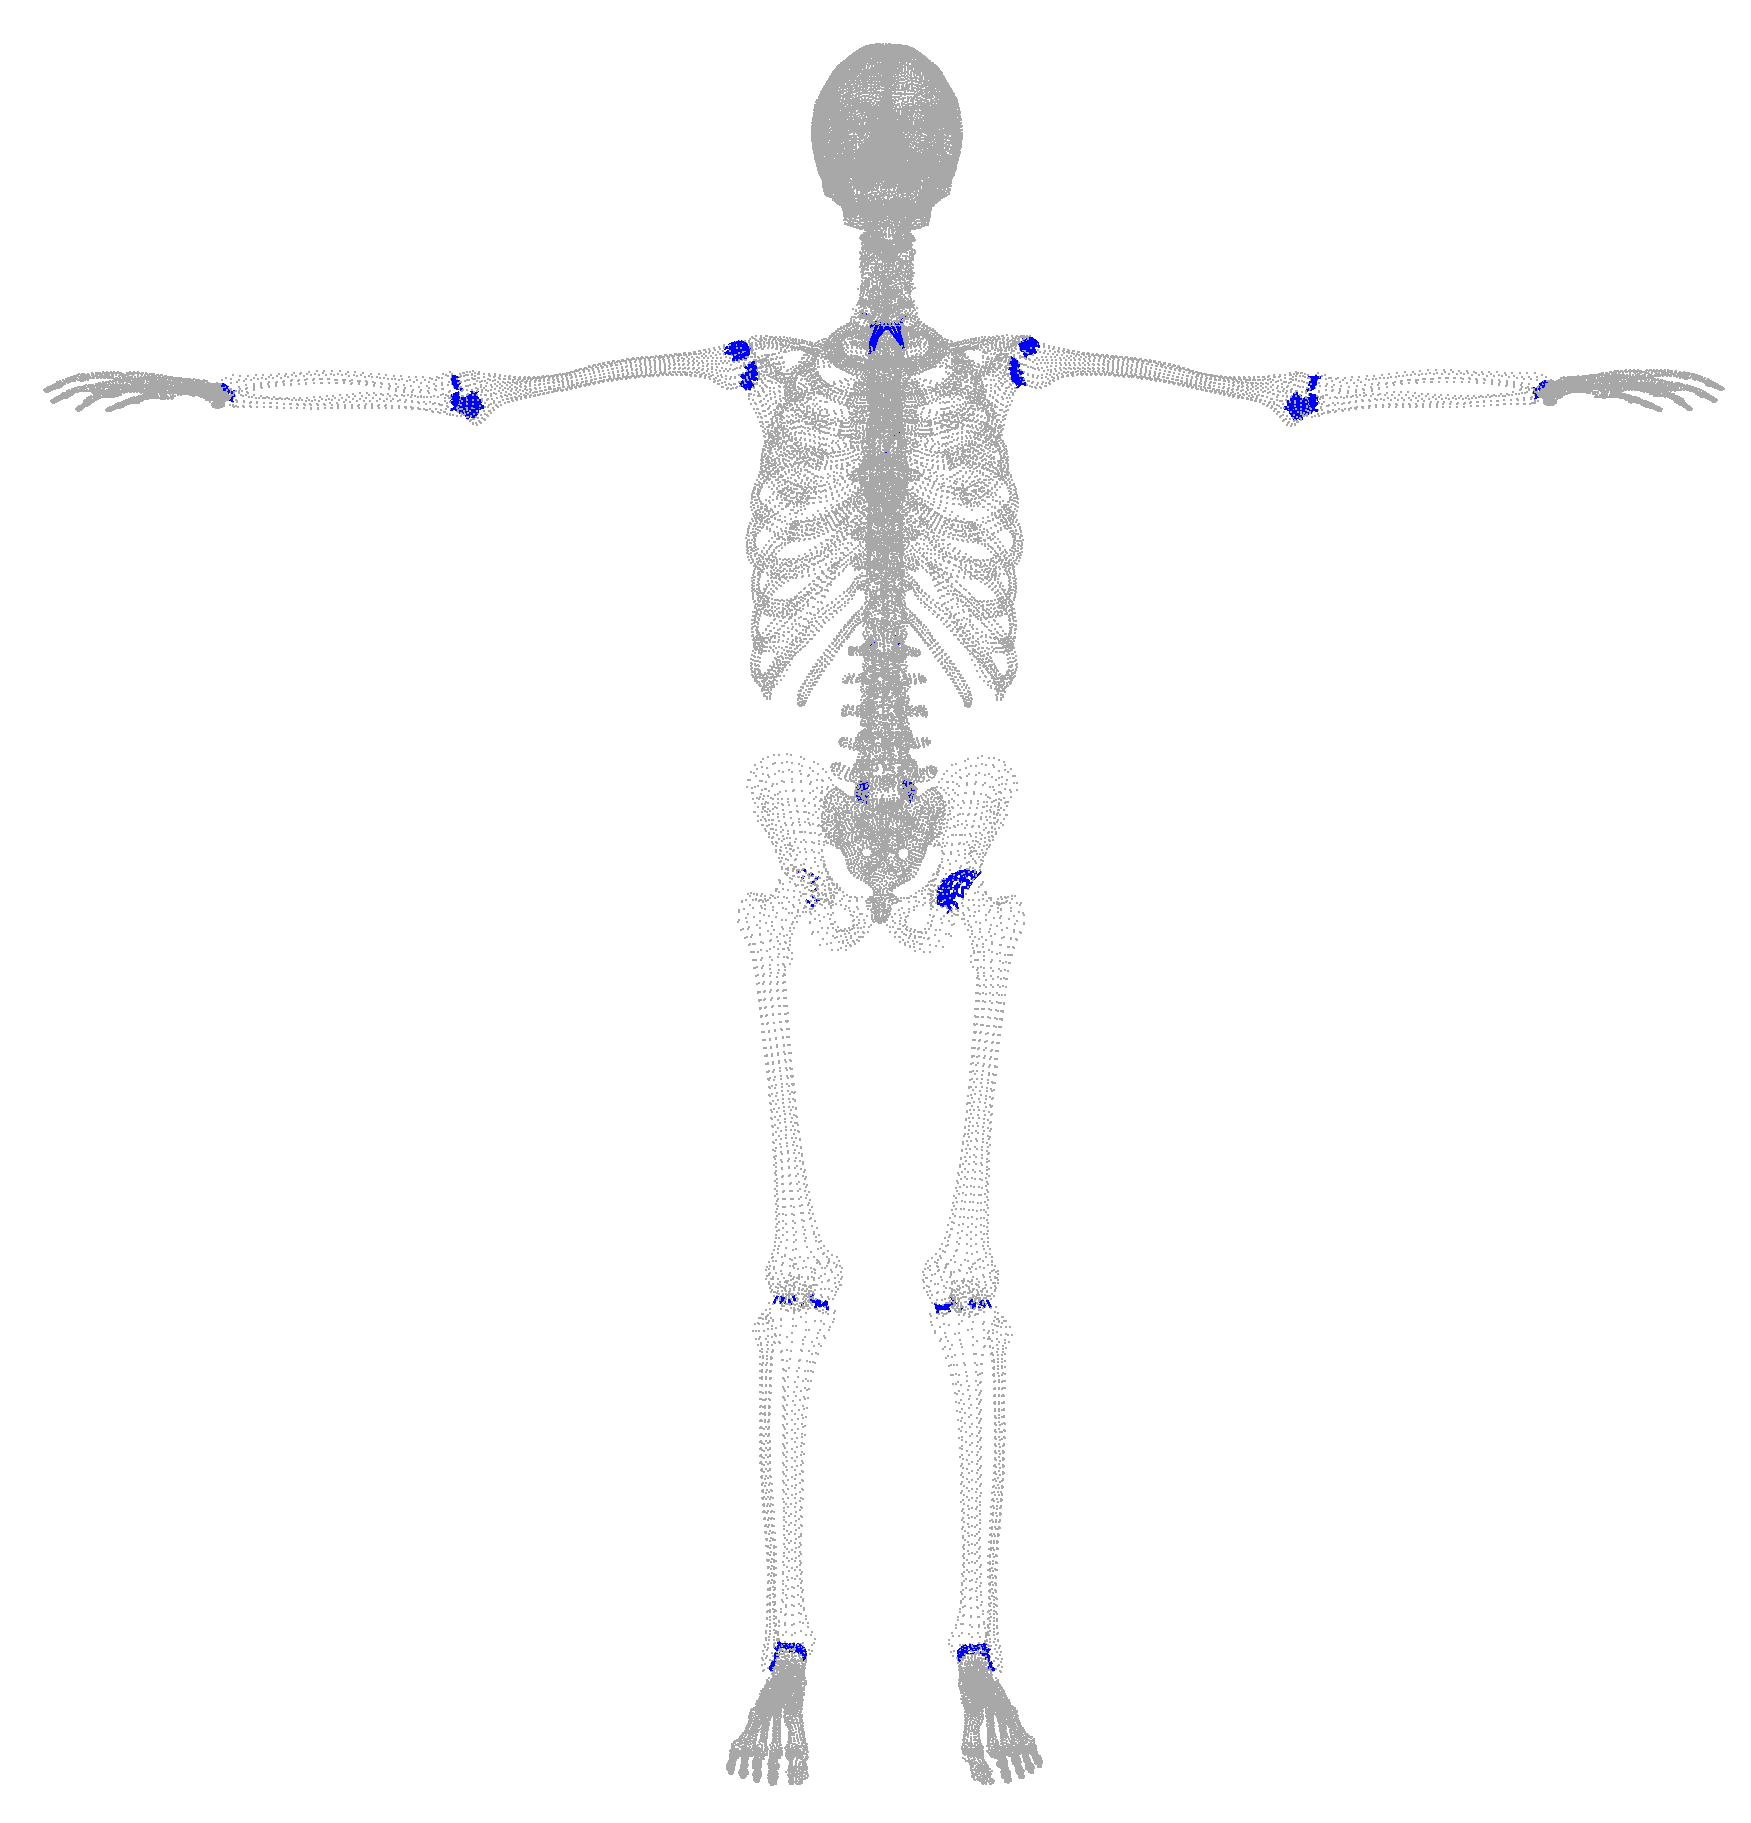

In this work, we address the problem of inferring the human anatomic skeleton, i.e. the bone shapes and locations, solely from surface observations. That is, we infer the bones from the skin. To that end, we learn a statistical model of the skeleton shape and its correlation with the skin surface (Fig. 1 left). Given a posed body, our method predicts the skeleton from the body shape, and poses it inside subject to anatomic constraints (Fig. 1 right).

In our skeleton model, we manually define 21 groups of bones that belong to the same anatomic part, and define the interfaces between these parts. In Fig. 10 we show the different parts with color codes, their interfaces, as well as the 3D landmarks defined on the bones.